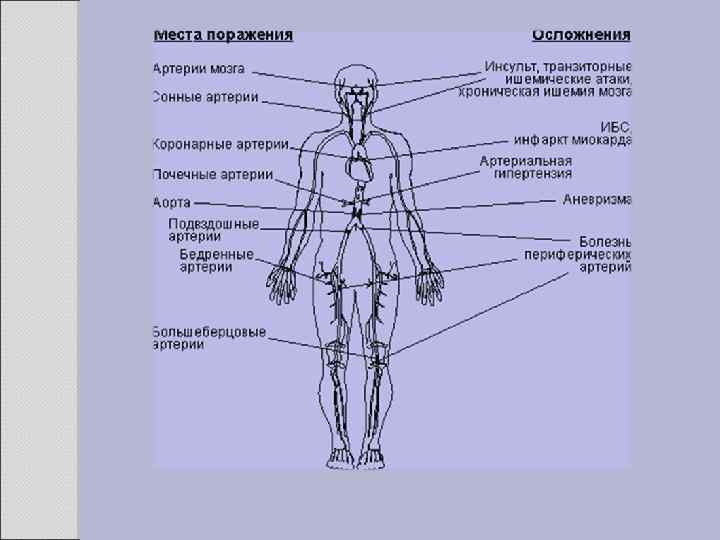

Клиника Клинические проявления часто не соответствуют морфологии. При патологоанатомическом вскрытии обширное и выраженное атеросклеротическое поражение сосудов может оказаться находкой. И наоборот, клиника ишемии органа может появляться при умеренной облитерации просвета сосуда. Характерно преимущественное поражение определенных артериальных бассейнов. От этого зависит и клиническая картина заболевания. Поражение коронарных артерий постепенно приводит к коронарной недостаточности, проявляющейся ишемической болезнью сердца. Заинтересованность церебральных артерий вызывает либо преходящую ишемию мозга либо инсульты. Поражение артерий конечностей — причина перемежающейся хромоты и сухой гангрены. Атеросклероз брыжеечных артерий ведет к ишемии и инфаркту кишечника (мезентериальный тромбоз). Также возможно поражение почечных артерий с формированием почки Голдблатта. Даже в пределах отдельных артериальных бассейнов характерны очаговые поражения — с вовлечением типичных участков и сохранностью соседних. Так, в сосудах сердца окклюзия наиболее часто возникает в проксимальном отделе передней межжелудочковой ветви левой коронарной артерии. Другая типичная локализация — проксимальный отдел почечной артерии и бифуркация сонной артерии. Некоторые артерии, например внутренняя грудная, поражаются редко, несмотря на близость к коронарным артериям и по расположению, и по строению. Атеросклеретические бляшки часто возникают в бифуркации артерий — там, где кровоток неравномерен; иными словами, в расположении бляшек играет роль локальная гемодинамика (см. патогенез).